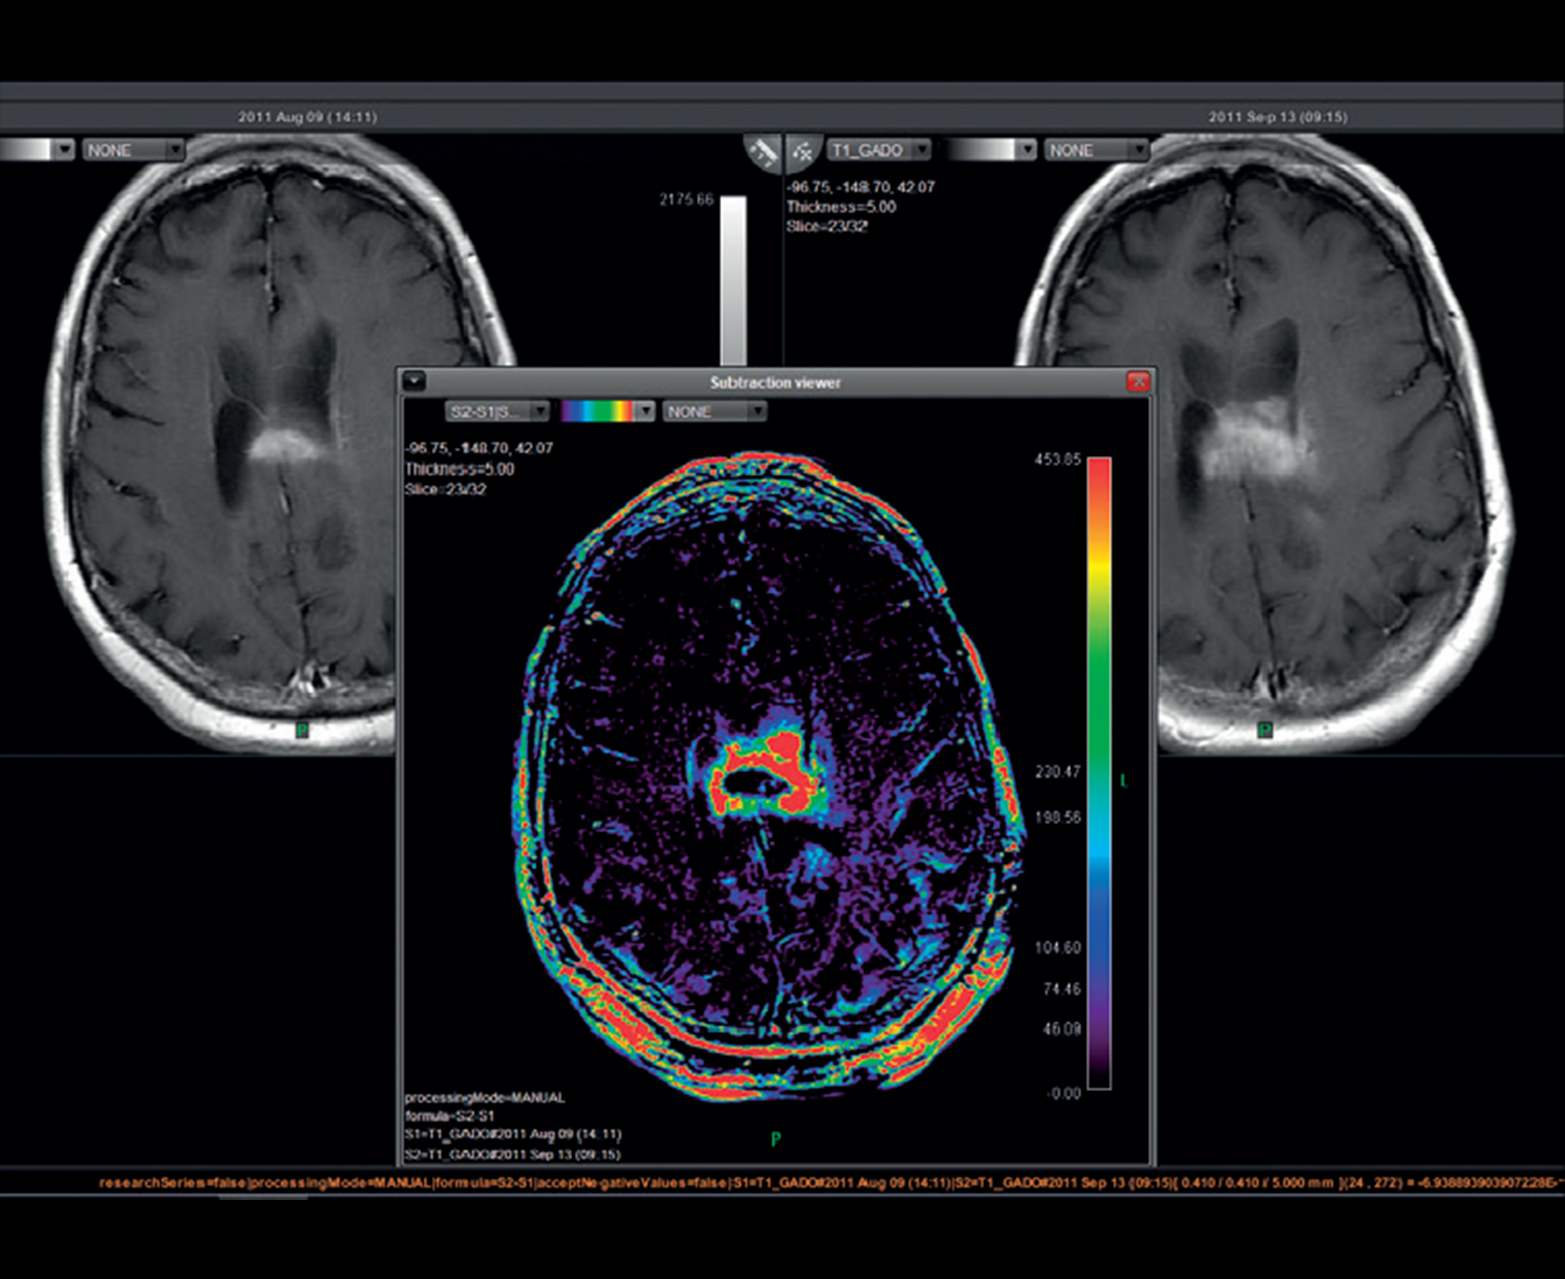

- Последующее наблюдение за развитием поражения и анализ ответа на лечение с временным вычитанием

Последующее наблюдение за поражением с совместной регистрацией